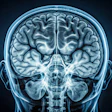

DTI-MRI measures the movement of water molecules in tissue and white-matter brain regions through fractional anisotropy to determine disruptions in flow. The lower the fractional anisotropy value, the more likely there is a microstructural abnormality.

DTI-MRI also allows researchers to reconstruct the main connections between different brain regions.

"Once we identify those tracts, we can estimate the quality of those connections, exploiting parameters obtained by the study of water diffusion," Carnevale explained. "With classic MRI, we only have information on the global structural integrity of white matter. Through this [DTI], we can isolate specific tracts and evaluate not only their structure, but also their functionality."

More specifically, the group with high blood pressure showed lower fractional anisotropy values in brain fibers in the anterior thalamus, affecting nonverbal skills; nerve fibers in the superior longitudinal fasciculus, which are involved with executive function and regulating emotions; and limbic system fibers of the cingulate gyrus, which are associated with attention tasks.

DTI-MRI illustrates the main tracts affected by hypertension. Reconstruction shows lower fractional anisotropy levels in regions including the anterior thalamic radiations, superior longitudinal fasciculus, and cingulate gyrus, resulting in significant deterioration in hypertensive patients. Image courtesy of Daniela Carnevale, PhD.And, if that wasn't enough, MRI scans also confirmed damage to the heart and kidneys among members of the high blood pressure group.